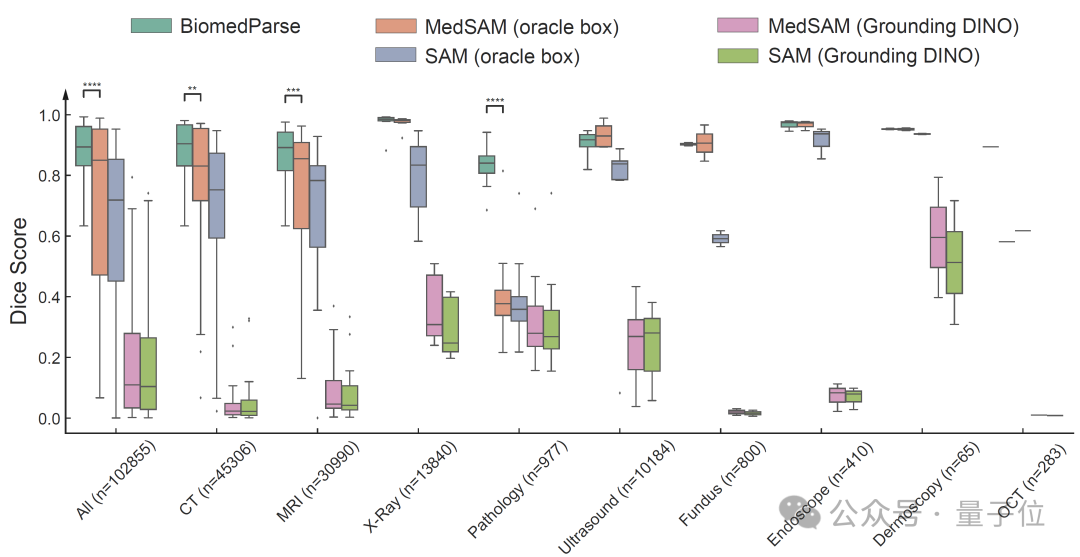

在测试集上,BiomedParse在Dice系数上显著超越了当前最优方法MedSAM和SAM,并且无需对每个对象手动提供边界框提示。

即使在给MedSAM和SAM提供精准边界框的情况下,BiomedParse的纯文本提示分割性能仍能超越5-15个百分点。

此外,BiomedParse的性能还优于SEEM、SegVol、SAT、CellViT、Swin UNETR等多个模型,尤其在复杂不规则的对象识别上表现突出。

生物医学图像中的不规则对象一直是传统模型的难题,而BiomedParse通过联合对象识别和检测任务,通过文本理解实现了对对象特定形状的建模。对复杂对象的识别精度远超传统模型,且在多模态数据集中进一步凸显了其优势。